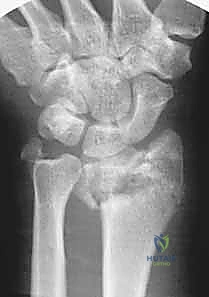

- الأشعة السينية (X-rays): بأوضاع متعددة لتقييم زوايا الكسر ومقدار الانهيار العظمي.

- الأشعة المقطعية (CT Scan) مع إعادة البناء ثلاثي الأبعاد (3D Reconstruction): وهي خطوة إلزامية في الكسور المعقدة. تتيح للدكتور هطيف رؤية كل شظية عظمية داخل المفصل بدقة متناهية والتخطيط للعملية الجراحية قبل دخول غرفة العمليات.

كسور عظم الكعبرة البعيد، خاصة تلك الناتجة عن حوادث قوية أو سقوط من ارتفاعات عالية، تمثل تحديًا طبيًا وجراحيًا كبيرًا. هذه الكسور تختلف تمامًا عن كسور الرسغ البسيطة التي قد تحدث نتيجة تعثر بسيط. في حالات الطاقة العالية، غالبًا ما تتسبب القوة الميكانيكية الهائلة في تهشم العظم وتفتته إلى قطع صغيرة (Comminution)، وتؤثر بشكل مباشر ومدمر على سطح المفصل الحساس (Intra-articular fractures).

الميكانيكا الحيوية للإصابة (Biomechanics of Injury)

في حوادث الطاقة العالية (مثل حوادث الدراجات النارية أو السقوط من السقالات)، يتم دفع عظام اليد بقوة هائلة داخل عظم الكعبرة، مما يؤدي إلى "انفجار" العظم من الداخل وتفتته (Pilon-type fractures). هذا التفتت يجعل العظم غير قادر على تحمل أي ضغط، وينهار على نفسه (Collapse).

الجزء "البعيد" من الكعبرة (Distal Radius) هو الجزء القريب من مفصل الرسغ. هذا الجزء مغطى بغضروف أملس يسمح للرسغ بالحركة في جميع الاتجاهات (الثني، البسط، الدوران). عندما تتعرض هذه المنطقة لطاقة عالية، لا ينكسر العظم فحسب، بل يتهشم الغضروف المفصلي، وتتمزق الأربطة الدقيقة المحيطة به.